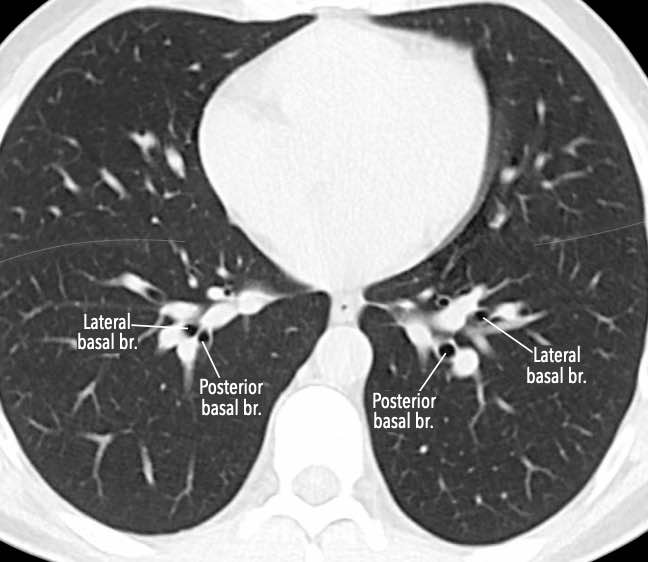

Phế quản trên CT

Cuộn qua các hình ảnh để quan sát khí quản phân chia thành phế quản chính phải và trái, sau đó tiếp tục phân chia thành các phế quản thùy và phế quản phân thùy.